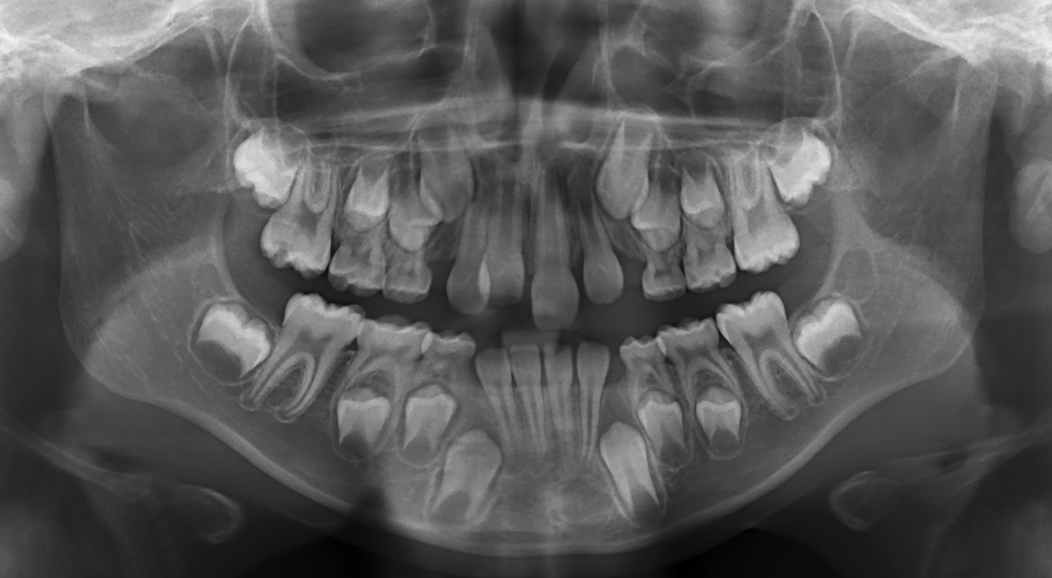

The following case illustrates the complete surgical/orthodontic treatment sequence for an impacted maxillary right central incisor. An 8½-year-old patient presented with a chief complaint of crowded teeth. The maxillary left central incisor was the only erupted incisor at the time of consultation (Figure 2 and Figure 3). Crowding was clinically diagnosed visually by the prominence of the unerupted right central incisor in the vestibule, and this was confirmed with a panoramic radiograph (Figure 4).

The maxillary right permanent centralincisor had a delayed eruption of 1½ years compared to its homologous incisor, and it was anteriorly displaced due to insufficient space in the premaxilla. Removal of the maxillary deciduous canines was indicated to unravel the crowding. An apically positioned flap of the impacted right central incisor was made to facilitate its eruption (Figure 5 and Figure 6). The case was worked up to plan an active phase l treatment, consisting of palatal expansion and the use of sectional fixed appliances in the upper arch. A transverse deficiency without posterior crossbite was identified, and therefore palatal expansion with a bonded expander was planned to widen the premaxilla (Figure 7 and Figure 8). A two-by-four fixed appliance system (brackets in the four maxillary anterior teeth and bands on the maxillary first molars) was used to align the maxillary teeth. The gingival margin of the retained maxillary right central incisor was slightly more apical than the left one, which erupted as expected (Figure 9 and Figure 10). Figure 11 shows a panoramic radiograph taken after completion of phase 1 treatment.

Fig 4. Initial panoramic x-ray.

Figure 4